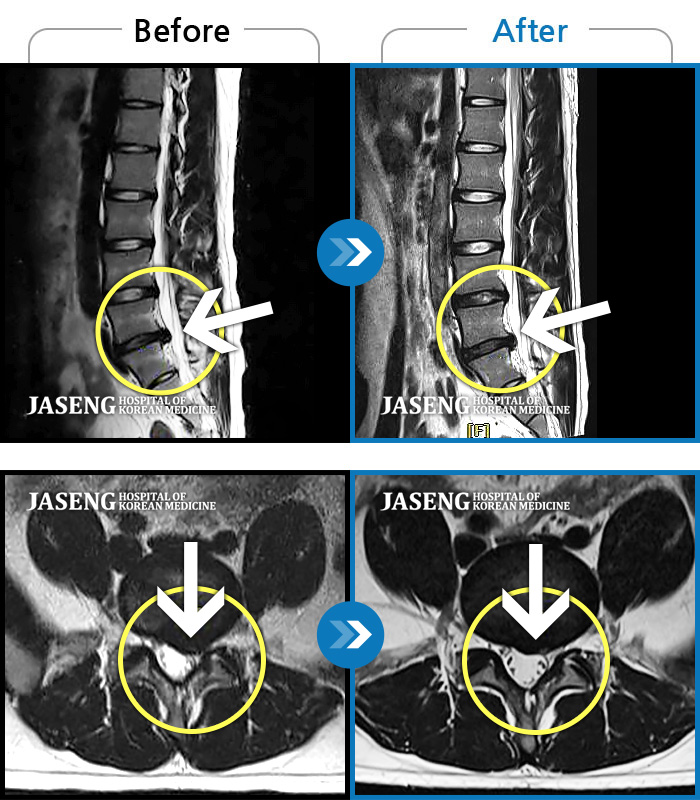

허리디스크

광주 · 김준수 원장

양측 허리 통증, 우측 다리까지 이어지는 통증과 저림, 모든 자세에서 통증 심화

촬영시기

2022.09.02 ~ 2024.08.02

2024.08.14

조회수 124